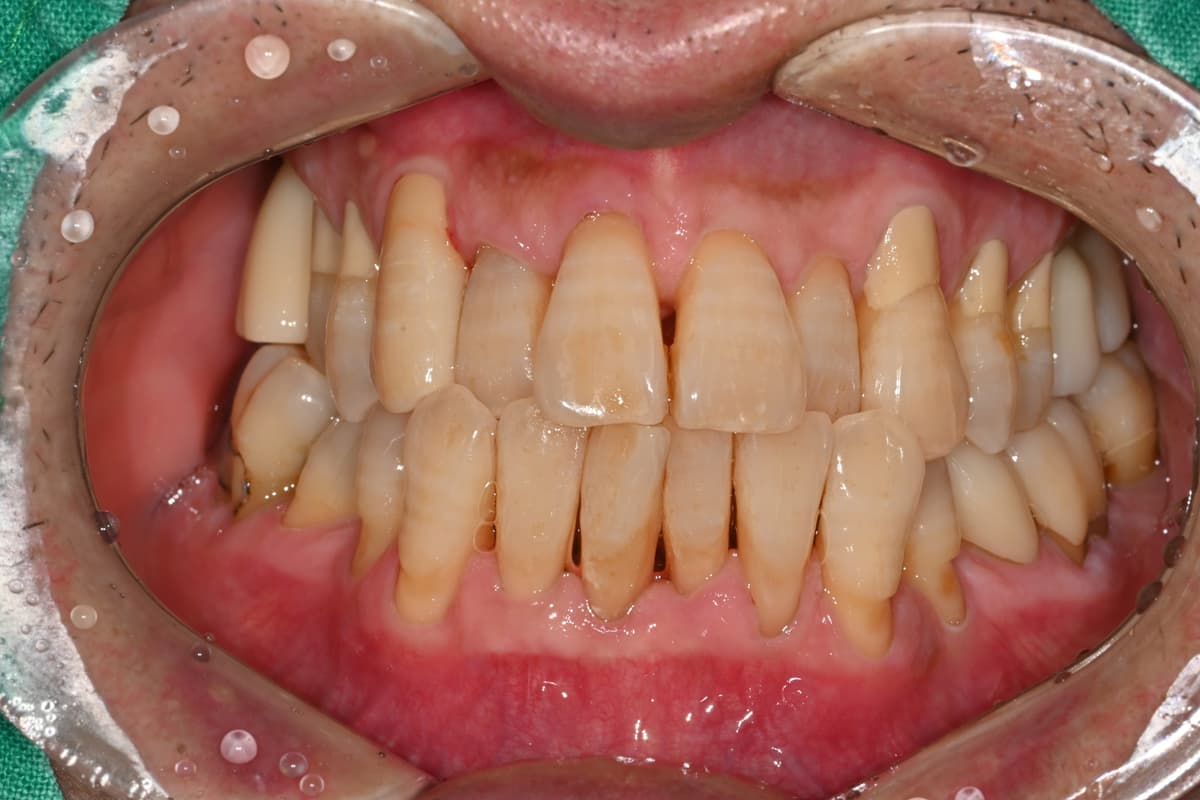

"정기적인 관리 덕분에

50대에도 모든 치아가 건강해요"

Before

After

치석과 잇몸 염증이 심했던 상태

정기적인 스케일링과 관리로 건강하게 유지